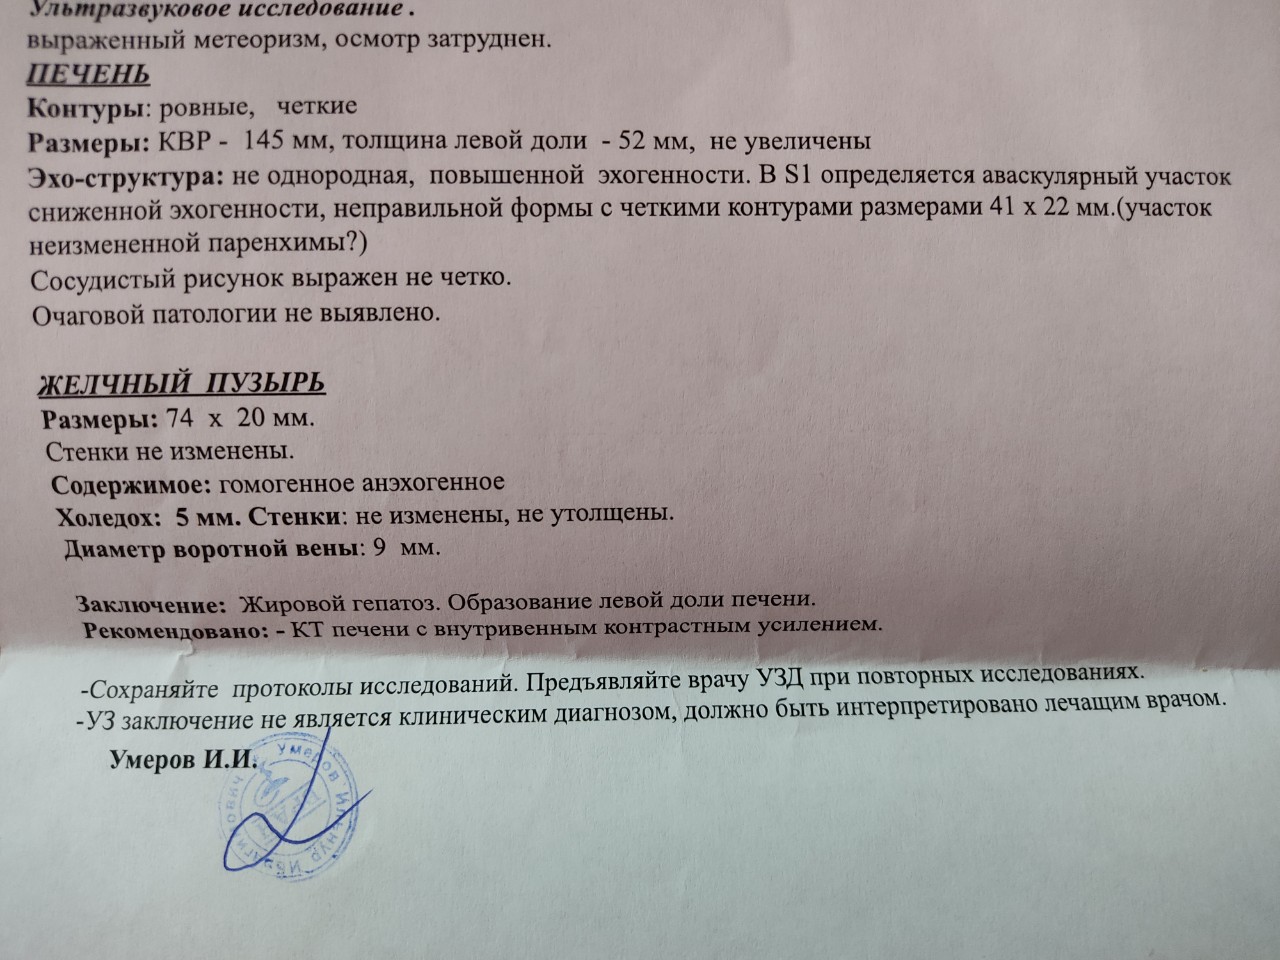

Как выглядит доля Риделя на УЗИ печени

Раздел: Иллюстрированный журнал